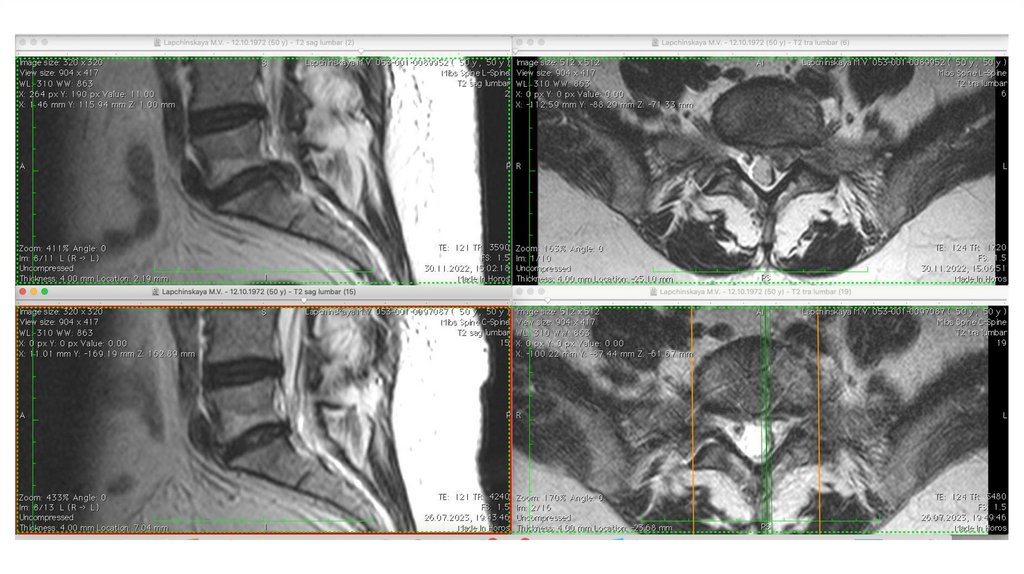

Спонтанный регресс грыжи

У некоторых пациентов может

наблюдаться уменьшение размеров грыжи

по результатам визуализационных

исследований . Данный феномен носит

название спонтанной резорбции

(регрессии) грыжи, которая может быть

как частичной, так и полной.

Однако частота регресса, условия его

развития, возможные механизмы и

влияние

на клиническую симптоматику остаются

не совсем ясными.

Ученые сделали вывод, что больные с

секвестрированными грыжами имеют

лучшие шансы на успешное

консервативное лечение, что,

вероятно, связано с воспалительной

19.